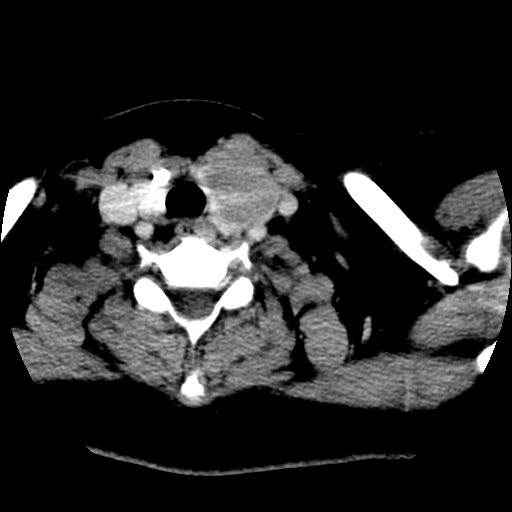

标题: CT25491:女,55岁,发现左侧甲状腺肿块一个月。 [打印本页]

标题: CT25491:女,55岁,发现左侧甲状腺肿块一个月。

女,55岁,发现左侧甲状腺肿块一个月,彩超示:甲状腺多发结节伴左叶结节液化。

左右叶都有,峡部也受累,有钙化,考虑结甲可能性大。

考虑左侧甲状腺结节性甲状腺肿,不排除甲状腺腺瘤。